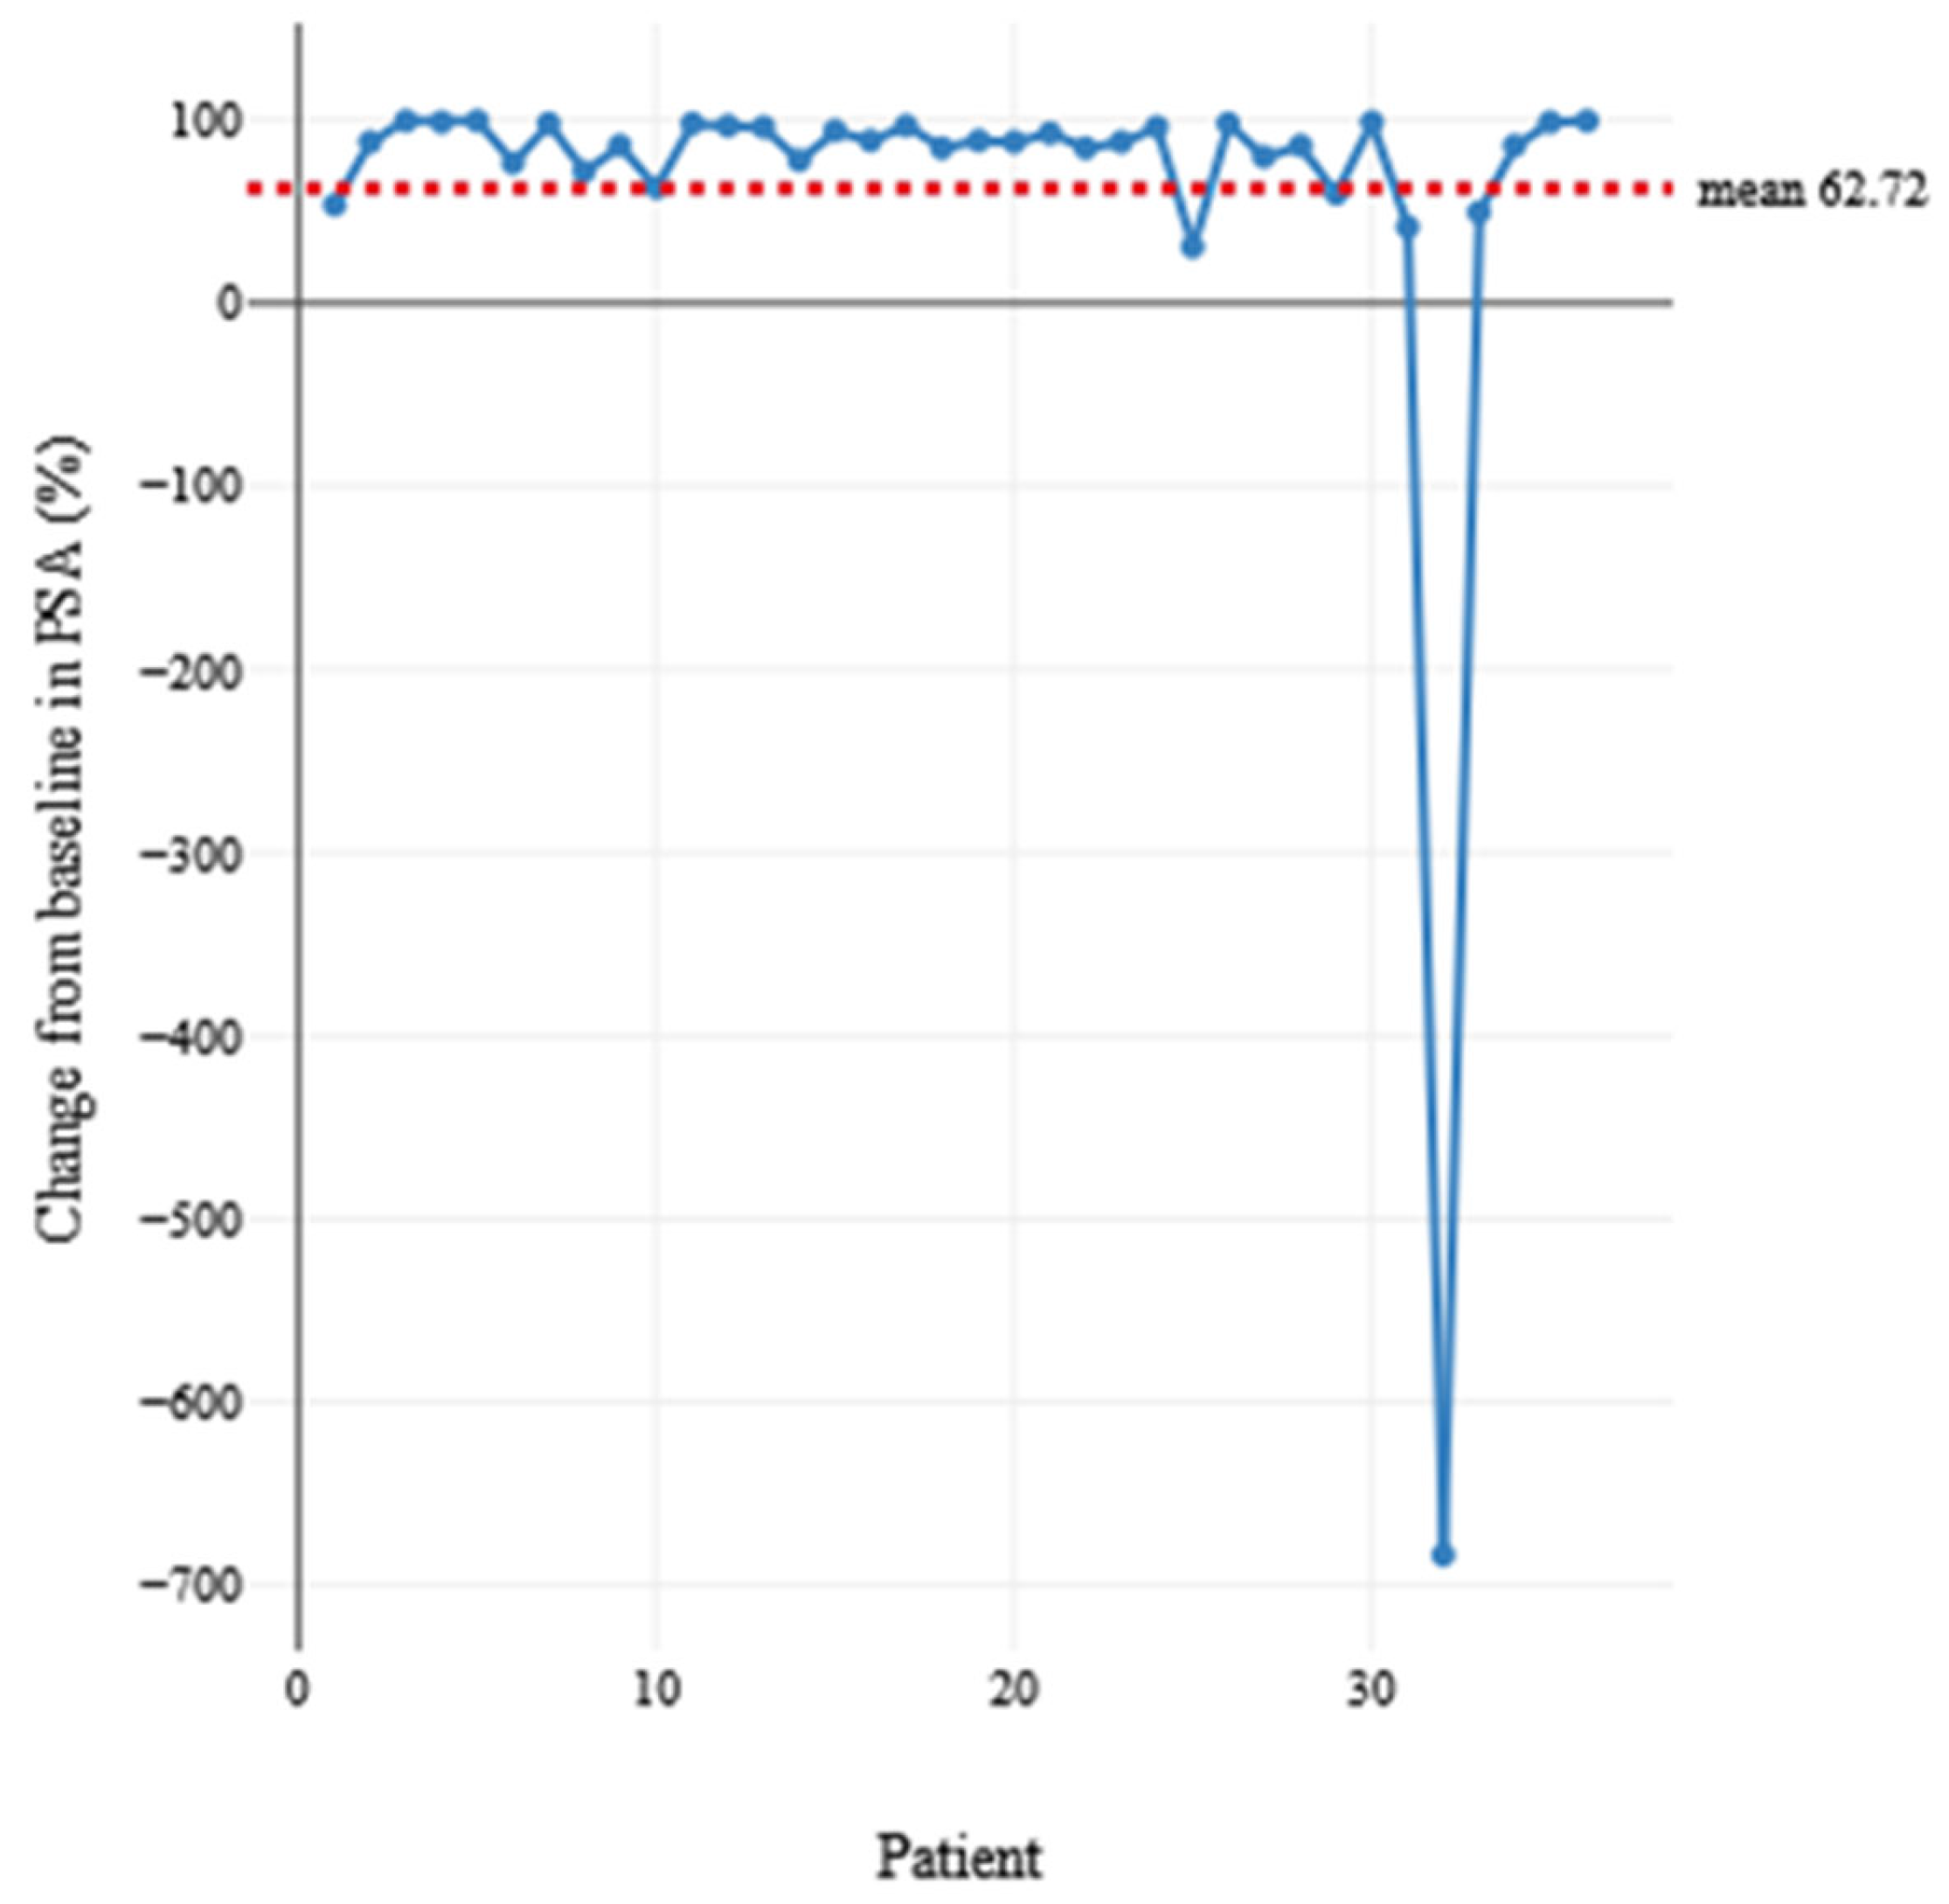

3. Results

| Mean | 71.78 | 2.81 | 17.44 | 175.15 | 31.51 | |

| Std. Deviation | 8.529 | 1.238 | 21.836 | 329.263 | 72.958 | |

| Percentiles | 25 | 65.25 | 2.00 | 4.00 | 9.44 | 0.33 |

| 50 | 71.00 | 3.00 | 11.00 | 56.95 | 2.51 | |

| 75 | 79.50 | 3.00 | 17.00 | 139.75 | 16.63 | |

| Baseline PSA (ng/mL)—PSA (ng/mL) at response | 143.64 | 274.920 | 45.820 | 50.627 | 236.666 | 3.135 | 35 | 0.002 | 0.003 |

| Baseline PSA | 390.74 ± 506.4 | 113.46 ± 186.9 | 58.18 ± 106.9 | 0.026 |

| PSA at response | 88.91 ± 112.3 | 13.20 ± 27.70 | 1.62 ± 2.75 | 0.004 |